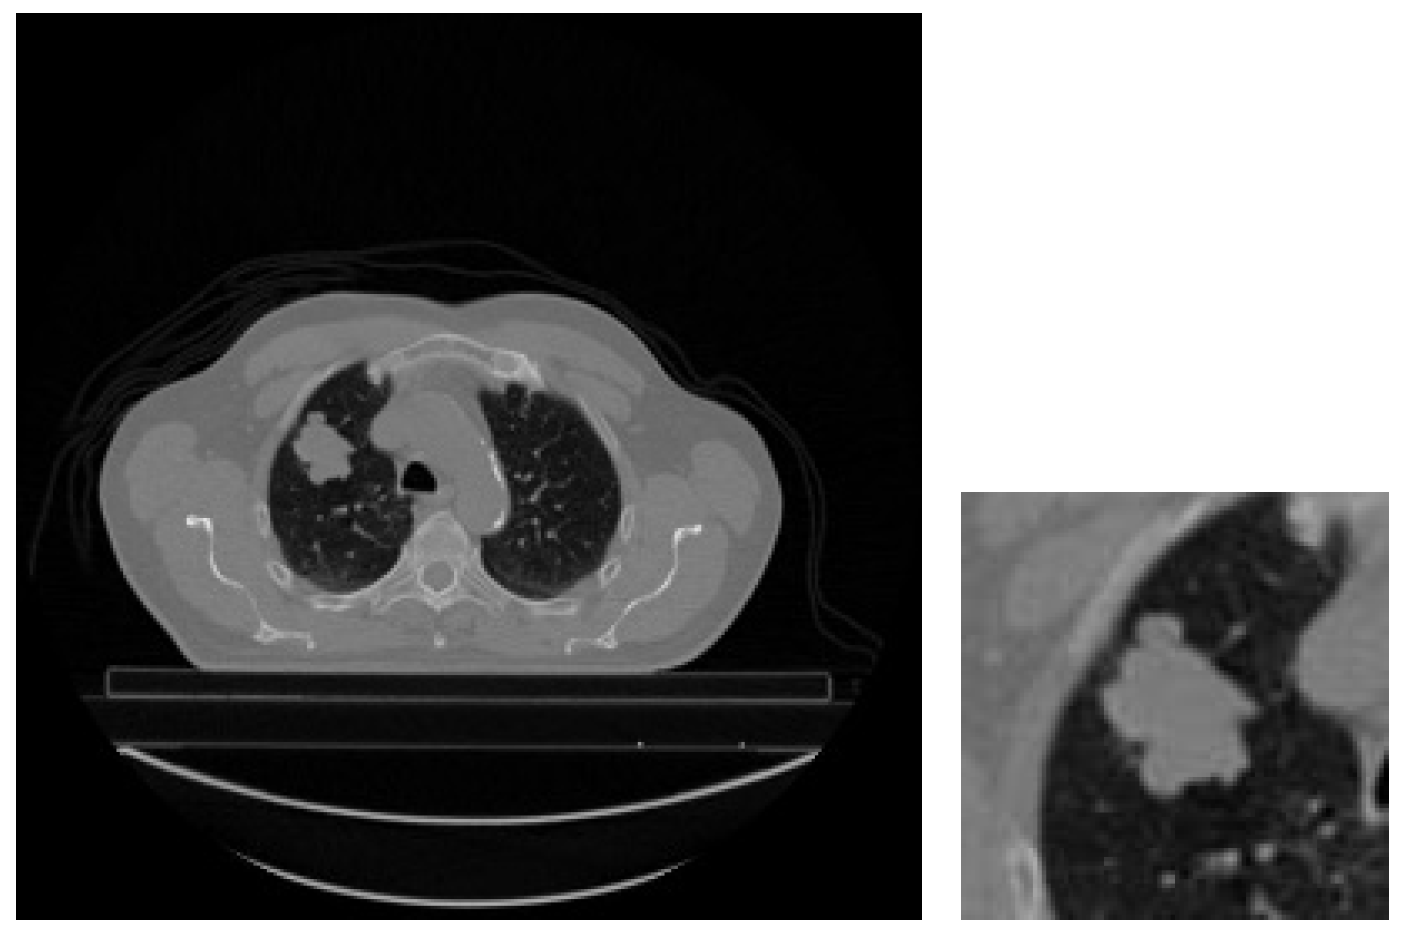

Effect of the Input Image: In the experiments, the main motivation was to facilitate a more efficient process by utilizing both the original versions of CT slices belonging to patients and cropped regions of interest (ROIs) corresponding to GTV-1 tumor areas. Within this scope, the initial step involves cropping the tumor regions from the images. This necessitates identifying the surroundings of the tumor regions within the CT slices containing GTV-1 tumors. Subsequently, the midpoint of the minimum rectangle surrounding the tumor region is determined using the endpoints of the tumor boundary. Finally, the tumor region is cropped to a size of 128 × 128 pixels with the midpoint of the rectangle as the center. Figure 11 illustrates the cropped tumor region alongside the CT slice containing the largest GTV-1 circumference for a patient (LUNG1-243).

Figure 11. Original slice and cropped image containing the largest GTV-1 tumor (LUNG1-243).